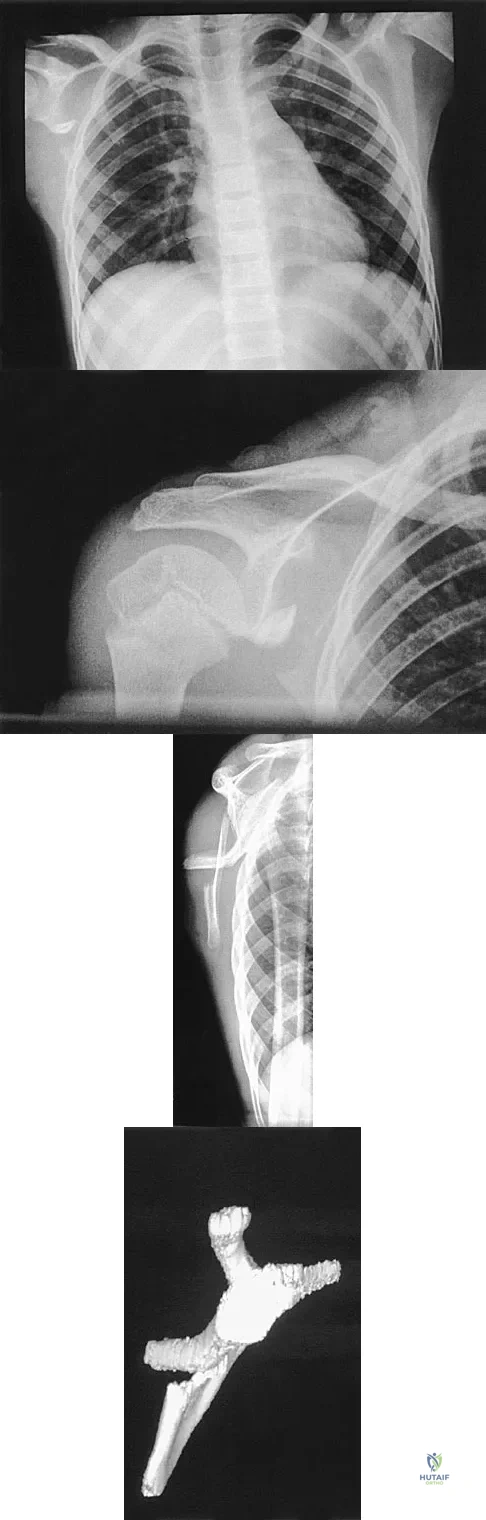

Figures 4a and 4b show the radiographs of a 53-year-old woman who was injured in a fall. After initial closed reduction, what is the preferred treatment for this fracture?

This elbow fracture-dislocation involves a radial head fracture, coronoid fracture, and ulnohumeral dislocation (terrible triad). Several algorithms exist for treatment; surgical treatment is indicated. The treatment should address the radial head. Studies have shown replacement to be superior to repair in comminuted fractures. The coronoid may be addressed in unstable cases at the time of radial head excision and replacement. Lateral ligamentous repair is carried out during closure of the lateral elbow capsule. Medial ligamentous repair also may be undertaken but usually in concert with bony repair. Hinged external fixation remains an option when instability exists following bony and soft-tissue repair. Acute ulnar nerve transposition is rarely indicated. Ring D, Jupiter JB, Zilberfarb J: Posterior dislocation of the elbow with fractures of the radial head and coronoid. J Bone Joint Surg Am 2002;84:547-551.

A 28-year-old man sustained a shoulder dislocation 2 years ago. It remained dislocated for 3 weeks and required an open reduction. He now reports constant pain and has only 60 degrees of forward elevation and 10 degrees of external rotation. He desires to return to some sporting activities. An AP radiograph and intraoperative photograph (a view of the humeral head through a deltopectoral approach) are shown in Figures 31a and 31b. What is the best treatment option to decrease pain and improve function?

The radiograph and intraoperative photograph show osteonecrosis with near complete head loss/collapse. A stemmed implant is more appropriate in this patient because there is very little bone to support a resurfacing implant. In a younger patient, a glenoid implant should be delayed as long as possible because of the eventual need for revision secondary to glenoid loosening and wear, especially in a young active male. The hemiarthroplasty may be converted to a total shoulder arthroplasty in the future. Levy O, Copeland SA: Cementless surface replacement arthroplasty of the shoulder: 5- to 10-year results with the Copeland mark-2 prosthesis. J Bone Joint Surg Br 2001;83:213-221.

What is the most appropriate treatment for a 50-year-old woman who sustains the injury shown in Figures 14a and 14b?

This intra-articular distal humerus fracture with displacement at the joint surface is best treated with surgical fixation. The most biomechanically sound construct is two plates applied to either column 180 degrees from one another. Elbow arthroplasty is most appropriate for low demand elderly patients. Schemitsch EH, Tencer AF, Henley MB: Biomechanical evaluation of methods of internal fixation of the distal humerus. J Orthop Trauma 1994;8:468-475. McCarty LP, Ring D, Jupiter JB: Management of distal humerus fractures. Am J Orthop 2005;34:430-438.